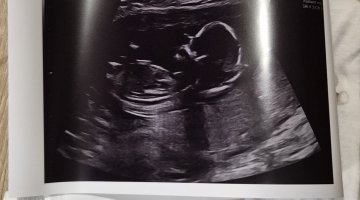

Sniker litt12+0 og alt så fint ut (enn så lenge). Veldig mye aktivitet, så var ikke lett å måle hjertefrekvensen «mye overskudd», sa jordmor

vil bare informere om at fullt navn og personnummer viser på bilde Vis vedlegget 456171

Lov å tippe kjønn om dere vil/ser noe![]()

JenteVis vedlegget 456171